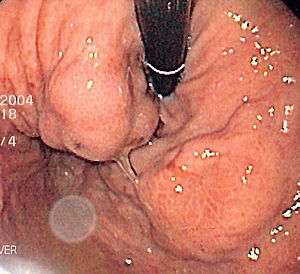

| Isolated gastric varices of Sarin classification IGV-1 seen on gastroscopy in a patient with portal hypertension | |

The Sarin classification of gastric varices identifies four different anatomical types of gastric varices, which differ in terms of treatment modalities.